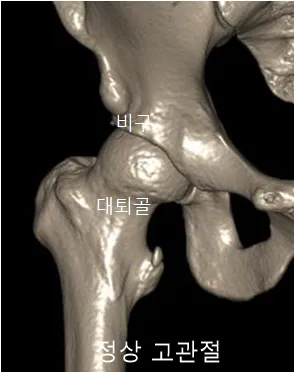

고관절을 이루는 비구(골반의 컵 모양 소켓)와 대퇴골두(허벅지 뼈의 공 모양 끝부분), 그리고 경부(대퇴골두와 허벅지 뼈를 연결하는 부위)의 구조가 서로 충돌하면서 통증을 일으키는 질환입니다. 관절 사이의 충돌이 오랜 기간 반복되면 충돌 부위의 관절 연골이 손상되고, 비구(소켓에 붙어 있는 연골)나 대퇴골에 붙어 있는 섬유 연골 조직이 찢어져 통증을 유발할 수 있습니다.